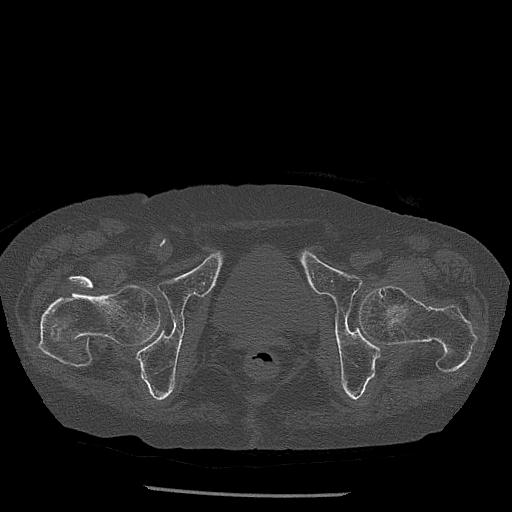

100703 1/27 両股正面+軸 1/29 両股正面+軸 94歳女性 パンソンロン

46666 1/28 両股正面+軸と 1/26 右手関節 2R 76歳女性 右転子部骨折

37 1/18 両股正面+軸 1/22 2R 86歳女性 右転子下

91569 3/25 両股正面とラウエン 70歳女性 人工骨頭+バンクーバー